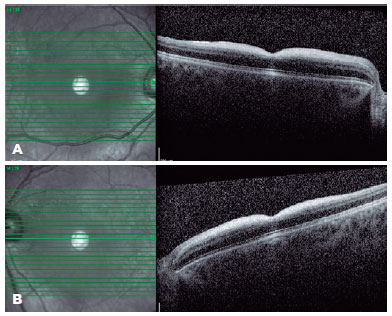

A 19-year-old female patient presented to our clinic with complaints of bilaterally decreased vision for the past 8 years. These complaints had been worsening within 5 years, which were thought to be fatigue, tremor, ataxia, and myoclonic epilepsy after simple daily activities. Her siblings had no history of neurological and ophthalmic diseases. Her best-corrected visual acuity was 20/125 on the right and 20/200 on the left. Slit-lamp examination revealed clear cornea in both eyes and multiple punctate opacities in both lenses. In the fundus examination, bilateral macular CRS was observed with its characteristic red fovea and pale macula (Figure 1). SD-OCT (Heidelberg Engineering, Heidelberg, Germany) imaging revealed hyperreflectivity of the inner retinal layers and increased hyperreflectivity on the photoreceptor layer in the foveola region (Figure 2). In the fundus fluorescein angiography (FFA), slight shading and mild hypofluorescence with a blurred appearance at the vessel borders were observed in the macula (Figure 3). The patient was referred to the neurology department, and various analyses were performed (Table 1).

On SD-OCT, the characteristic finding of CRS is increased reflectivity of the inner retinal layers and photoreceptor layer in the fovea(5). Varela et al. measured reflectivity in OCTs of seven patients with sialidosis and galactosialidosis using grayscale analysis (Fiji/ImageJ2) and compared with healthy volunteers. They detected a significant increase in reflectivity in the inner retinal layers compared with the control group(6). Similarly, our case demonstrated hyperreflective nerve fiber layer and ganglion cell layer on which the boundaries could not be clearly determined (Figure 2). In sialidosis, oligosaccharides containing sialic acid accumulate in the ganglion cells(7). As the foveal region is relatively free of ganglion cells, it maintains its redness and causes a CRS appearance. Some studies claim that CRS appearance is caused by increased retinal nerve fiber thickening(8). Similar findings can be found in other metabolic storage diseases. In patients with Niemann-Pick type B, SD-OCT showed hyperreflective areas on the retinal surface, except for the foveal depression area(9).

The hyperreflective appearance on the photoreceptor layer in the foveolar region is attributed to the relatively hyporeflective appearance of the outer retinal layer caused by the increased reflectivity of the inner retinal layers in the vicinity(10).